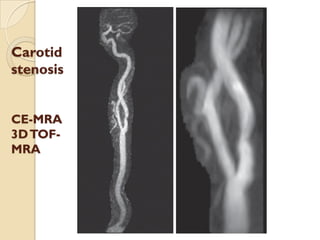

 Initial screening test is noninvasive , either DS or MRA.

 TOF MRA is less sensitive DS (75%Vs 87%) but more specific

(88%Vs 46%).

 Concordance in TOF and DS is more sensitive(96%) and specific

(85%) than either test alone.(Johnston, and Goldstein et al 2001)

 2DTOF MRA over estimates the degree of stenosis.

 3DTOF MRA is less likely to overestimate stenosis.

 Combination of 2D and 3DTOF MRA results in greater

specificity.

 ‘FLOW GAP’- segmental dropout , When the stenosis is more

than 70%. ( Heiserman JE et al 1996)

 3D CEMRA have greater anatomical coverage in terms of

surface morphology, carotid bifurcation, near occlusion

 3D CE MRA is more sensitive(94.6% vs 91.2%) and specific (

88.3%vs 91.9%) thanTOF MRA for high grade ICA stenosis.

Carotid atherosclerotic narrowing

Carotid stenosis

2D TOF MRA 3D TOF MRA DSA

Carotid

stenosis

CE-MRA

3DTOF-

MRA